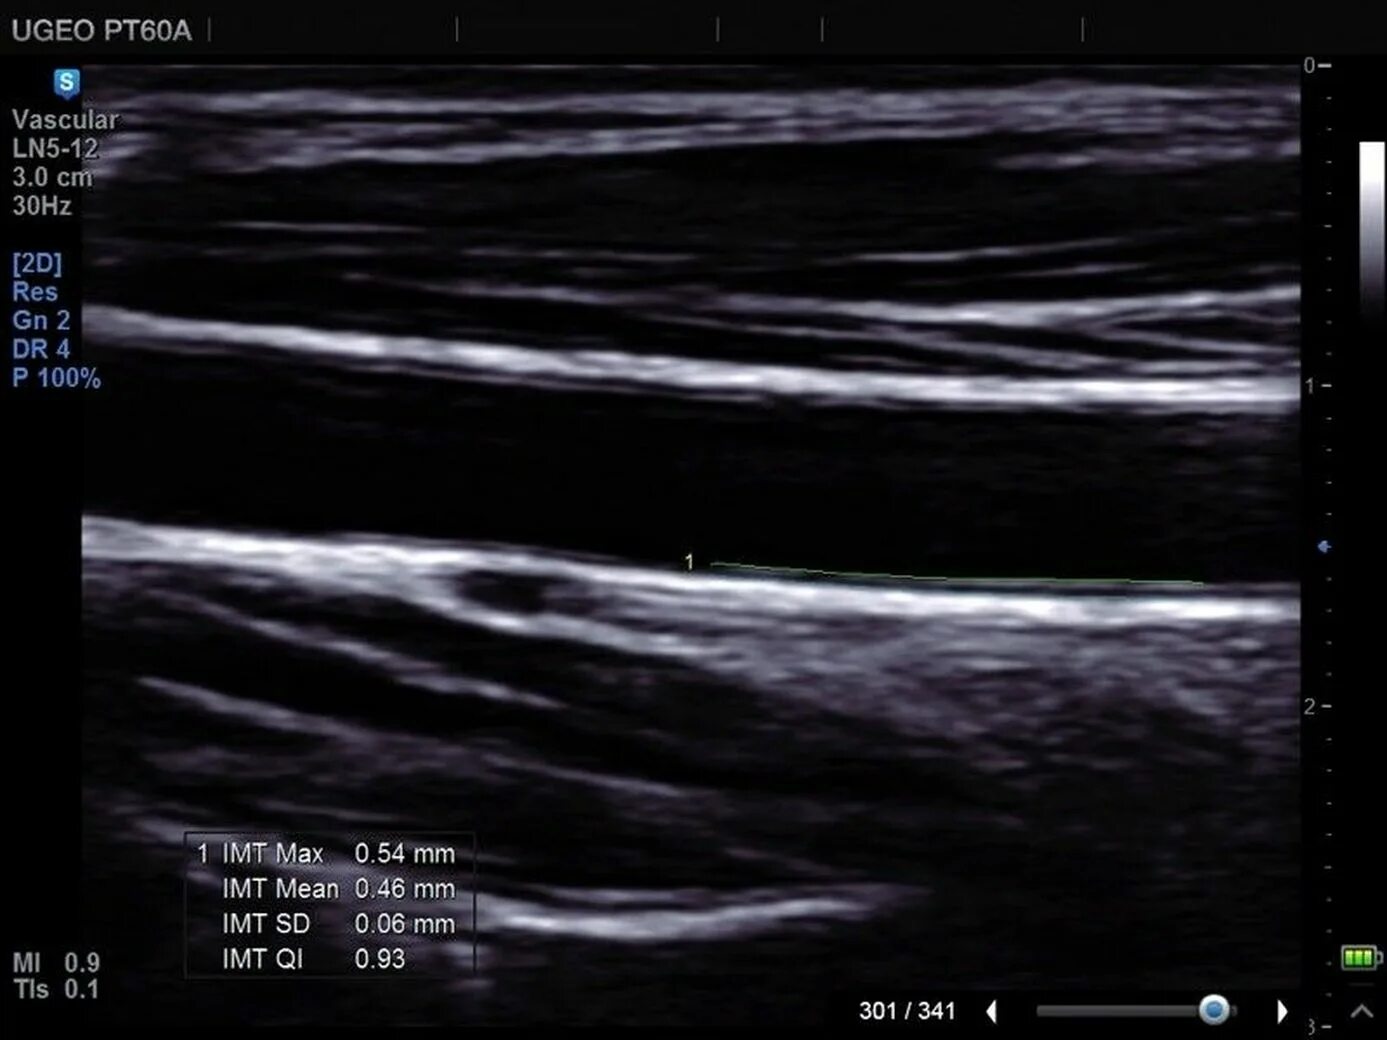

Сделать узи сонной артерии